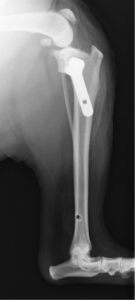

21のサーキュラーソーにて骨切りし、φ2.7mmのTPLOプレート(シンセス社製)にて固定しました。

術後レントゲン

術後のTPAは5度であった。